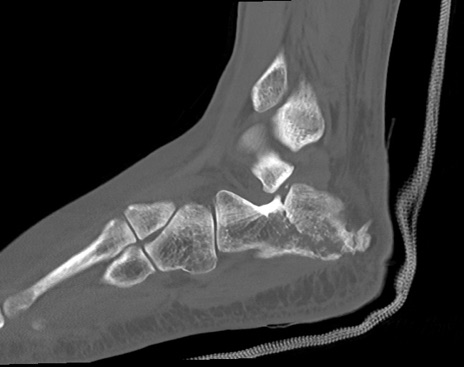

症例37 左足関節CT(矢状断像)

左足関節CT

冠状断像